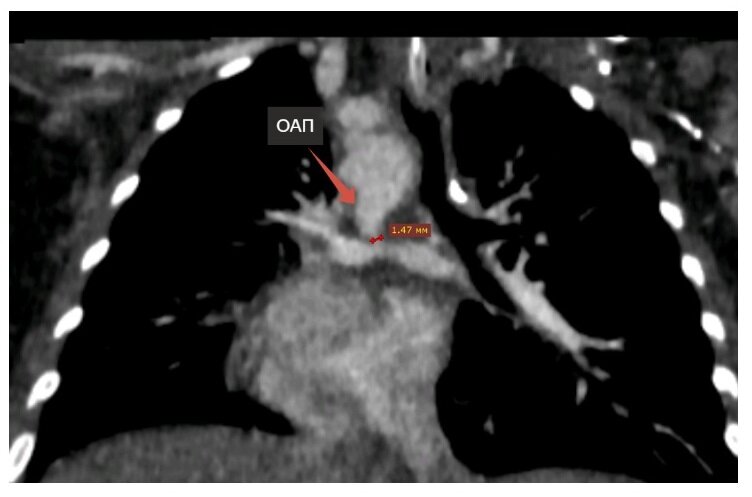

Несмотря на острое течение у ребенка вирусной инфекции, хирурги Центра Мешалкина провели экстренную операцию – через сонную артерию завели катетер внутрь открытого артериального протока и расширили его с помощью стента, обычно используемого для коронарных артерий у взрослых.